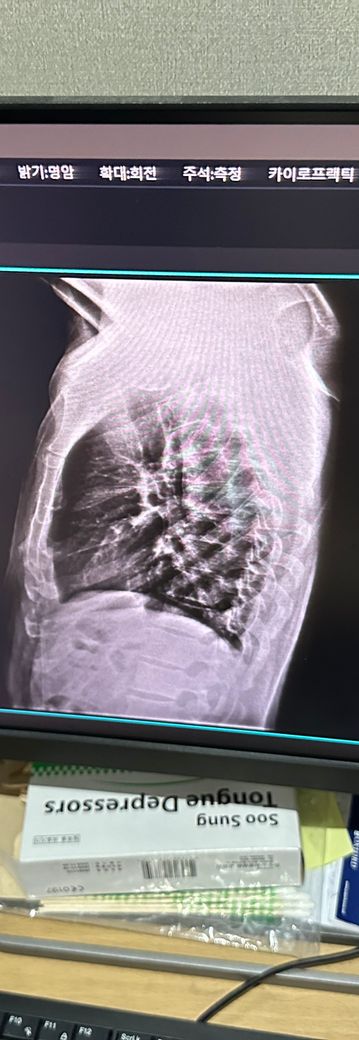

사진은 증상 생기기 일주일정도 전에 정형외과에서 찍은 사진입니다

• 1번 째 사진

엑스레이 사진을 다각도로 봐야겠지만 이 사진으로만 보기에는 흉추측만증이 있으신것 같네요 그로인해 옆구리 통증이 올수 있습니다